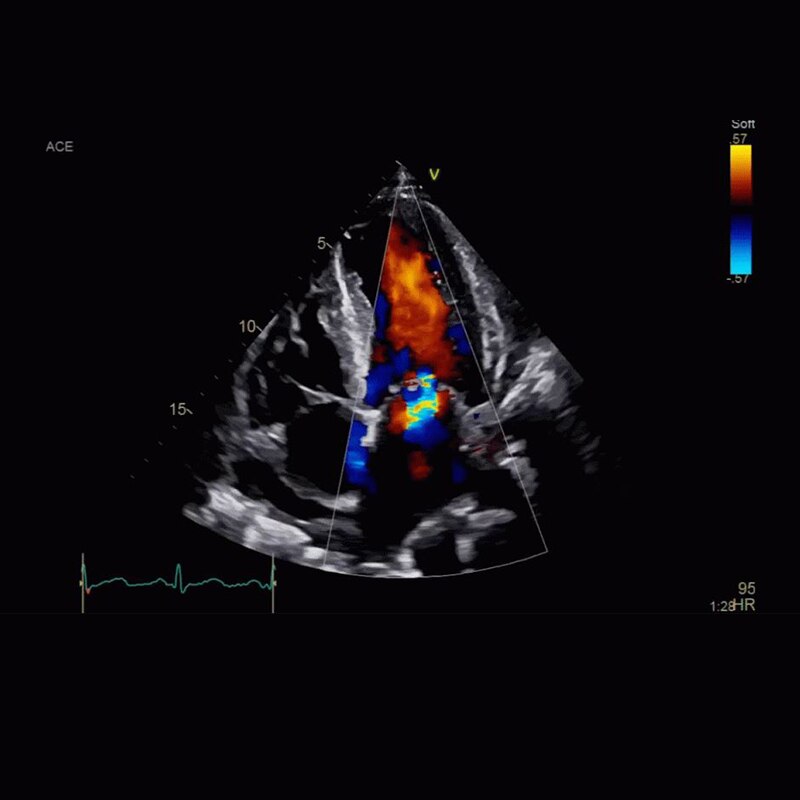

Vivid Portfolio

Cardiac Auto Doppler automatically provides Doppler measurement results for the most common parameters, with minimal user guidance.  Read More

Vivid E95

cSound beamforming technology for exceptional visualization quality with impressive resolution in 2D, color flow, Doppler and 4D formats. Read More

Provides instant access to predefined (factory or user created) 4D views during live mode to potentially provide more consistent data while reducing scanning time. Read More